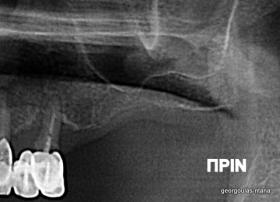

Η ασθενής αυτή είχε παλιές ακίνητες αποκαταστάσεις (γέφυρες) στην άνω γνάθο  κ μια κινητή προσθετική αποκατάσταση (μερική οδοντοστοιχία-"μασελάκι") στην κάτω γνάθο. Ήταν δυσαρεστημένη τόσο με την εμφάνιση όσο και με τη λειτουργία των δοντιών της καθώς παραπονιόταν ότι  είχαν εντονη κινητικότητα ενώ και οι προσθετικές τους εργασιές δεν ήταν σταθερές. Η πρόγνωση των δοντιών κρίθηκε φτωχή με αποτέλεσμα να μην είναι δυνατή η συμμετοχή τους σε μια νεα προσθετική αποκατάσταση με μακροχρόνια διάρκεια. Η ασθενής επιθυμούσε οι νέες αποκαταστάσεις να είναι σταθερές και ακίνητες.  Για το λόγο αυτό αποφασίστηκε η ολική αποκατάσταση της άνω κ κάτω γνάθου με ακίνητες επιεμφυτευματικές εργασίες. Στην αριστερή πλευρά της άνω γνάθου, λόγω μη επαρκούς οστού για την τοποθέτηση εμφυτευμάτων προηγήθηκε επέμβαση ανοιχτής  ανύψωσης ιγμορείου άντρου με τη χρήση πιεζοχειρουργικού μηχανήματος ώστε να δημιουργηθεί το κατάλληλο οστικό υπόστρωμα. Ακολούθησε σε επόμενο χειρουργείο η εξαγωγή των υπάρχοντων δοντιών κ η άμεση τοποθέτηση εμφυτεύματων (άμεση εμφύτευση) κ δύο μέρες μετά η τοποθέτηση προσωρινής εργασίας επί των εμφυτευμάτων (άμεση φόρτιση) με αποτέλεσμα η ασθενής να μη μείνει καθόλου χωρίς δόντια κ να είναι καλυμένη αισθητικά όσο καιρό διήρκησε η εργασία